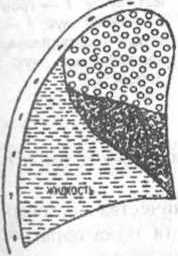

Reakcióvázlat atelectasia következtében fellépő összenyomás a tüdőszövet váladék.

Meg kell jegyezni, hogy a fájdalom és a köhögés tüneteinek váladékos mellhártyagyulladás kifejezve nem annyira tisztán, mint a száraz formában. A fájdalom általában egyfajta gravitációs és lehet akut ritkán. Köhögés annak a ténynek köszönhető, hogy a gyulladást hatással idegvégződéseket, amelyek membrán lap tüdő mellhártya. Azt is az oka, hogy a mechanikai tömörítés a hörgők, ha van spadenie tüdőszövet - atelectasia, hatása alatt a folyadék, amely szintén egy erős nyomást a szervezetben.

Élénkebben, mint a fenti tünetek, légszomj jelenik meg. Nehézlégzés légszomj. Úgy tűnik, annak a ténynek köszönhető, hogy része a tüdőszövet - parenchymának- közvetlenül részt gázcsere miatt folyadékgyülem nyomás megszűnik betölthesse.

Tompítás (váladék) fehér.

Fontos az is, hogy végezzen röntgen vizsgálata a beteg az oldalsó pozícióban. Ha exszudatív folyadék így kényszerült, lehetséges, hogy megszüntesse azt osumkovanie, azaz mozgásukban korlátozott képződése miatt a sűrű „falak” a kötőszövet, és az átmenet a gyulladásos folyamat krónikus.